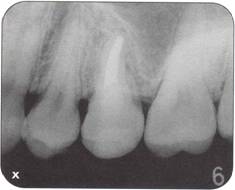

Fi 545e45f g 5-1d Preoperative periapical radiograph. |

|